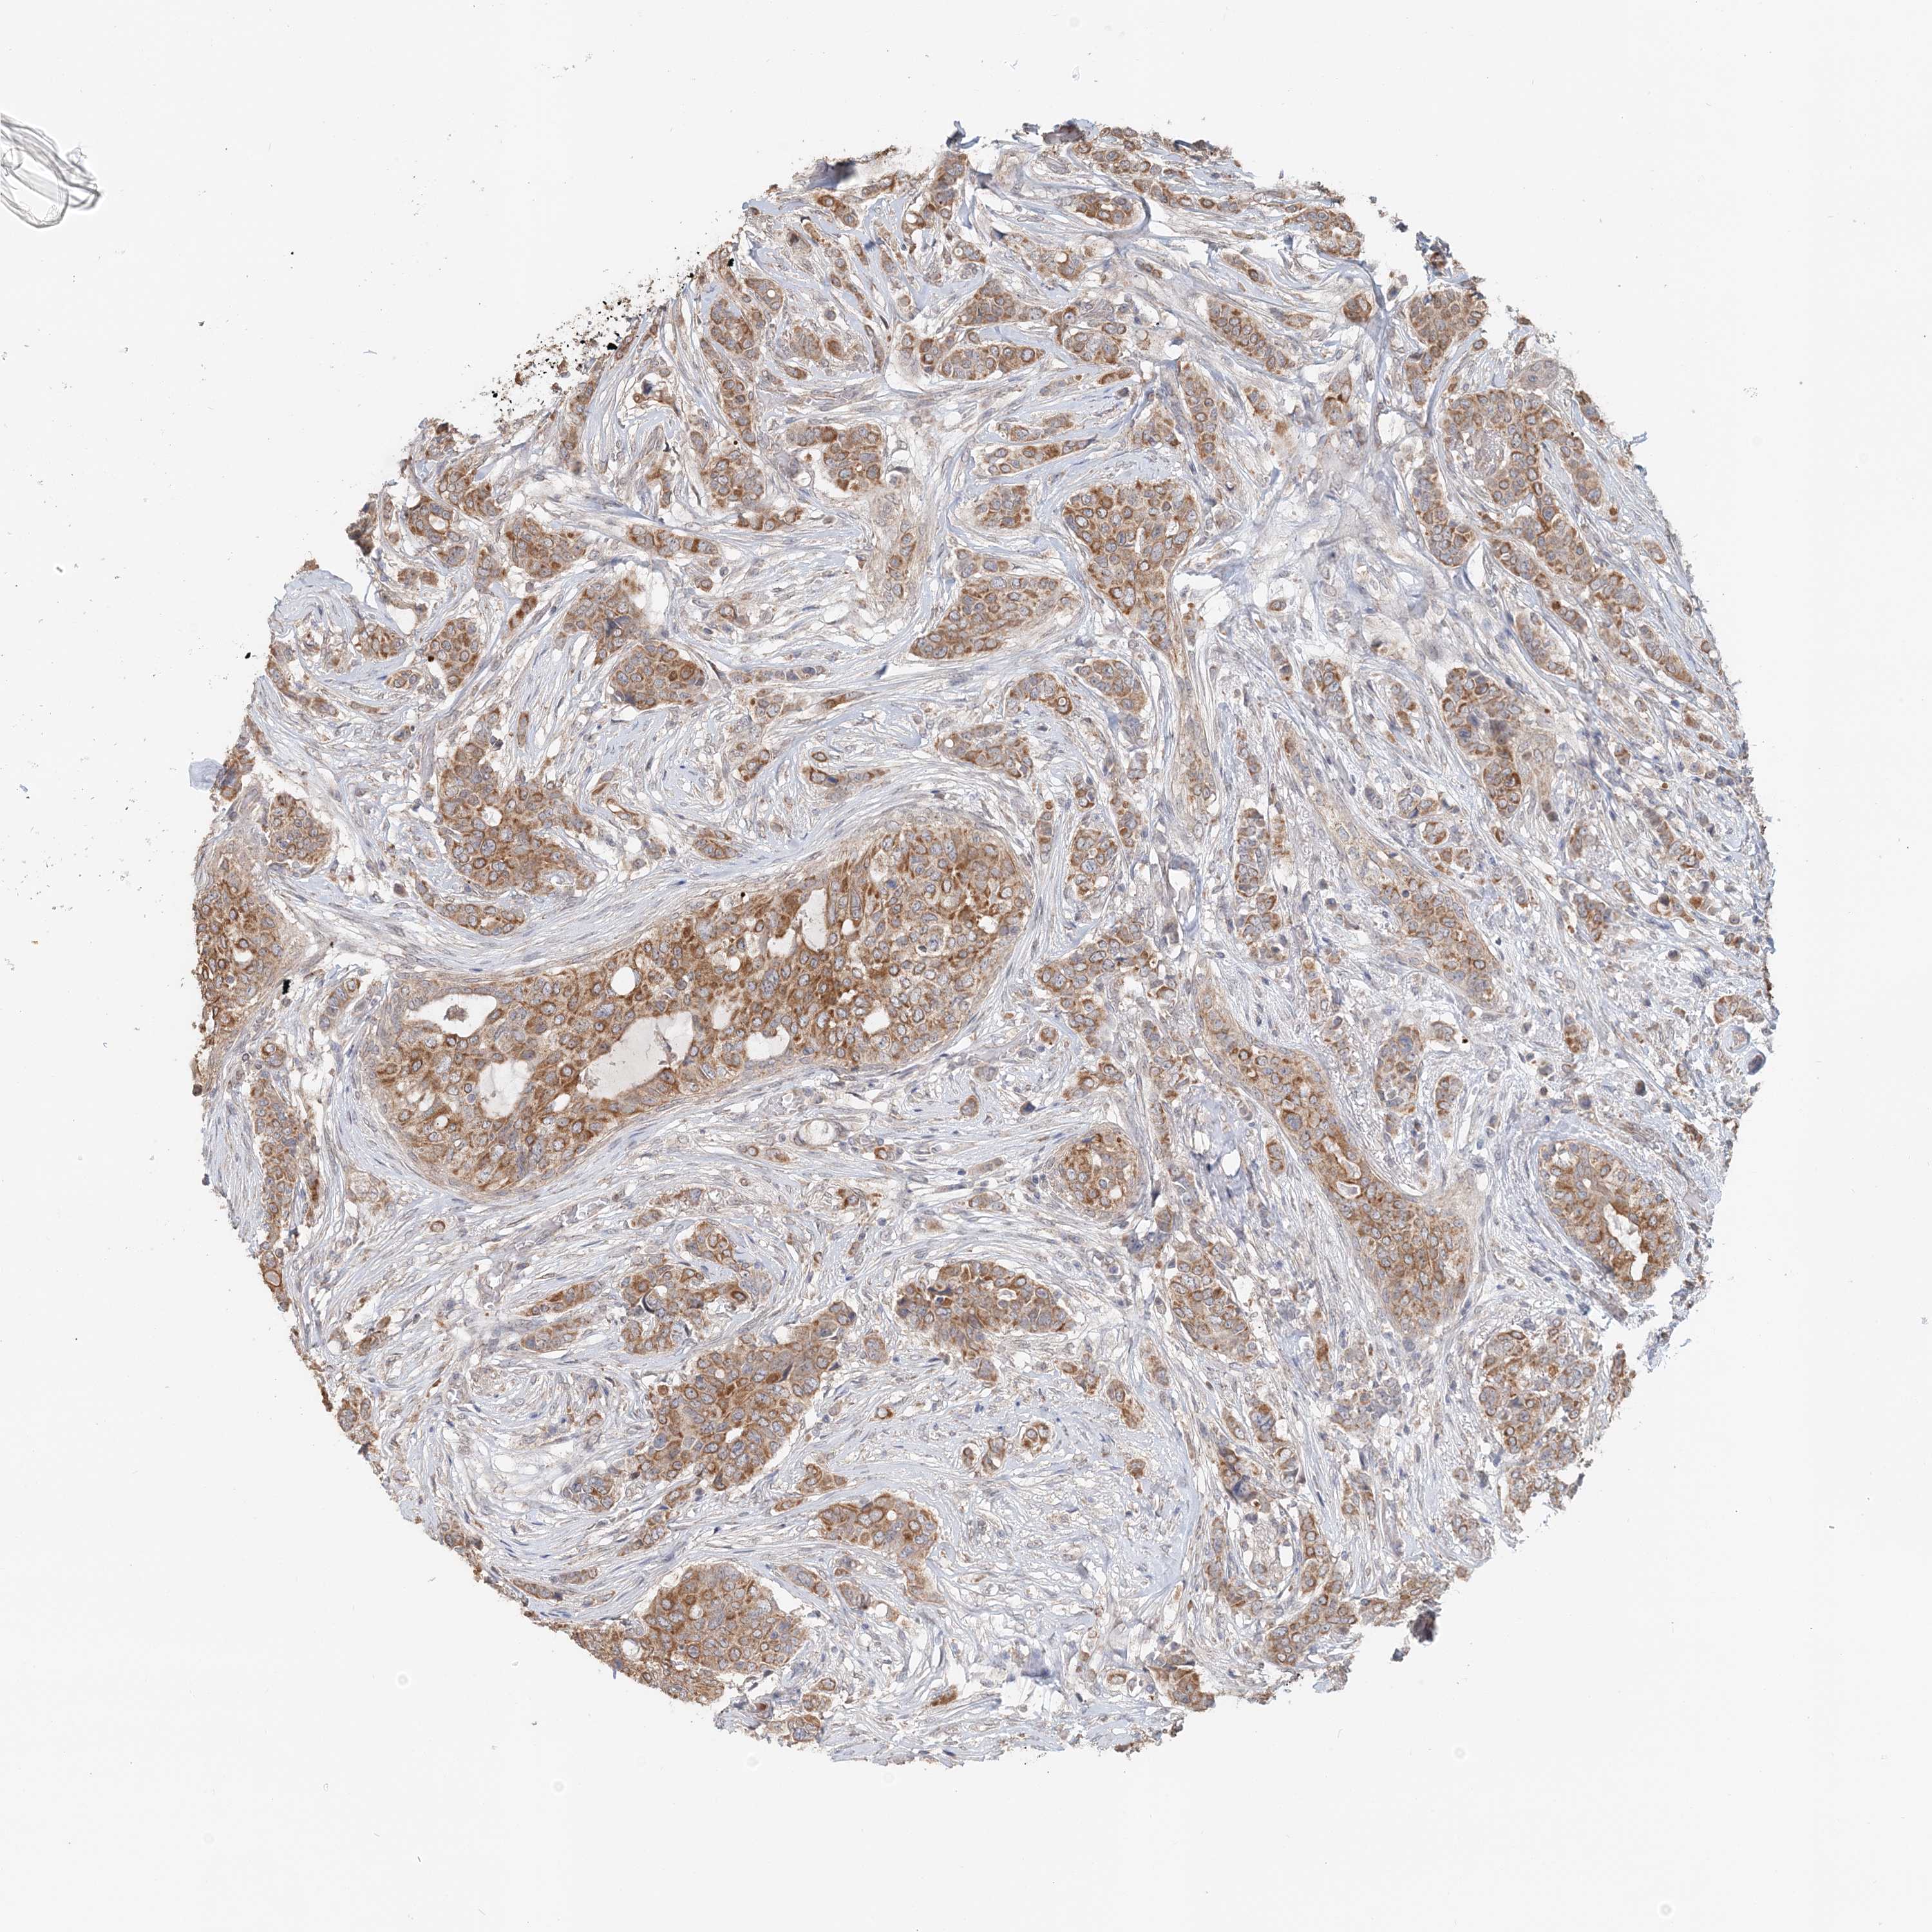

CANCER BREAST CANCER Show tissue menu

BRCA TCGA BRCA VALIDATION PROTEIN EXPRESSION

Breast cancer

Human cancer